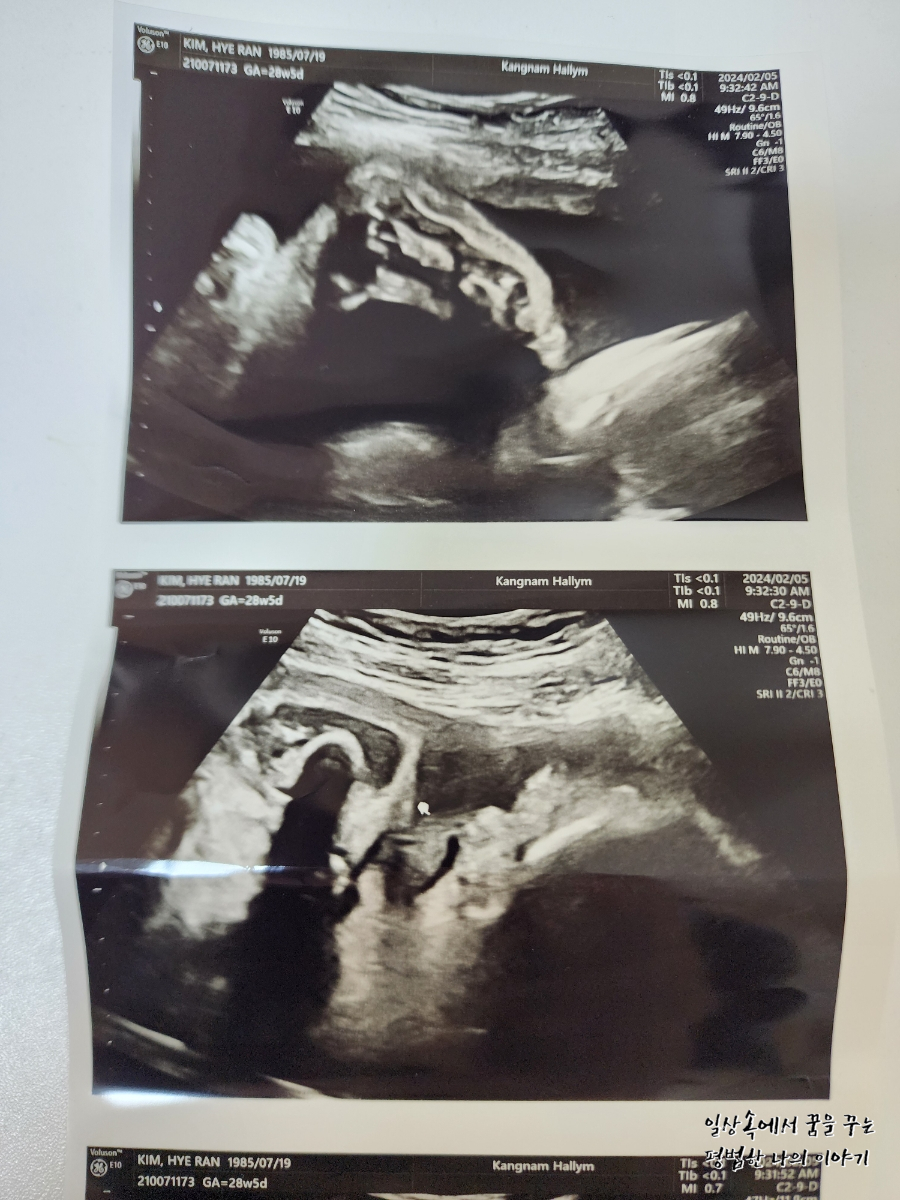

CL(Cervical Length, 자궁경부 길이): 정상

AF(Amniotic Fluid, 양수): 정상

이번에 오랜만에 보는 초음파라 얼굴이라도 볼 수 있으려나 내심 기대하고 갔는데 얼굴을 아래쪽으로 향한 채로 뒤돌아 있어서 얼굴 보기가 쉽지 않았다. 그나마 막판에 두 손으로 얼굴을 살짝 가린 채 하품하고 있는 모습을 보여줬다. 남편 말로는 첫째보다 볼살이 더 많은 것 같다며 왠지 첫째보다 더 클 것 같다고... 무럭무럭 잘 자라줘서 고마워.